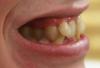

Repby Опубликовано 5 января, 2011 Поделиться Опубликовано 5 января, 2011 Здравствуйте!Мне 37 лет. Прошу помочь определиться с тактикой лечения:1) Какую брекет-систему использовать? Имеет ли преимущество система Damon в моем случае?2) Есть ли возможность провести лечение без удаления зубов?3) Единственная 8-ка снизу слева - ее удаление планируется по терапевтическим показаниям. Это поможет исправлению нижней челюсти?Спасибо. Ссылка на комментарий